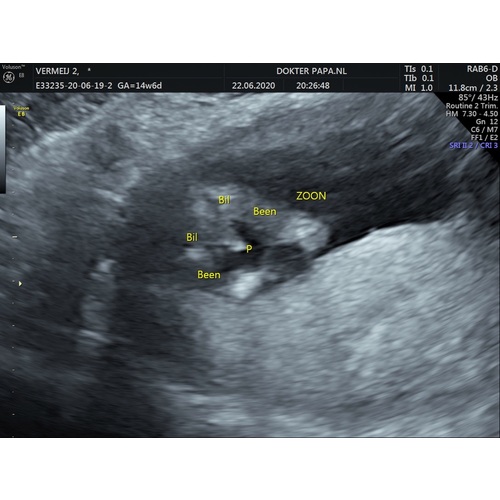

Nooit ervaring gehad met echo's, ben voor het eerst zwanger en bij een jongen was het niet te missen🤣 bij mij zag je echt dat piemeltje en balletjes hihih

Bij jou zie je duidelijk 2 beentjes uit elkaar en het piemeltje dat naar links wijst en de balletjes ertussen 😍 gefeliciteerd!

Als ik kijk naar mijn echo zie ik duidelijk het verschil

Oh grappig! Ook uit Apeldoorn :) ik zie nu eindelijk op jouw echo wat ik op mijne ook zie, van die uitstekende streepjes. Bij alle andere echo’s zag ik alleen maar “plat” tussen de benen. Vond mijne niet overtuigend eerst